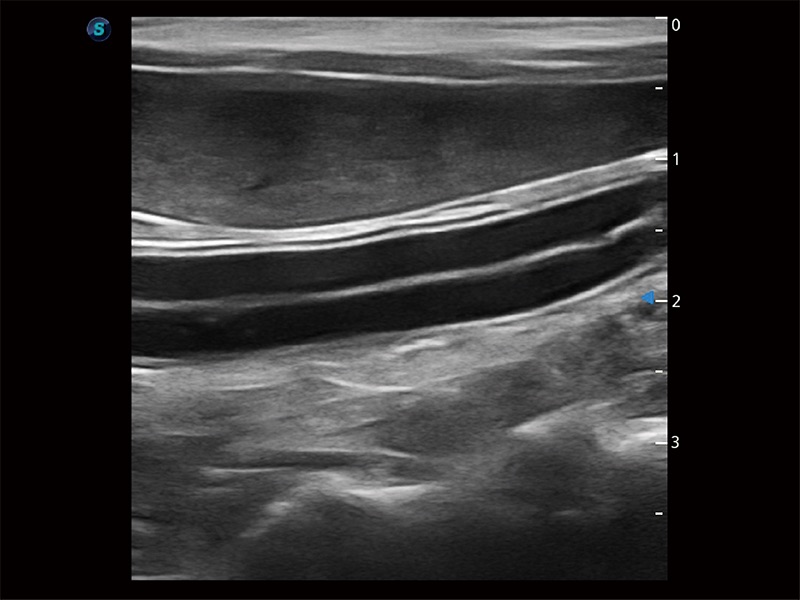

极大提升超低速微细血流的检出能力,同时更精准地滤除软组织和超声信号,为兽用医生提供以往无法通过常规血流获得的疾病诊断信息。

操作简便,无需高频度外力作用即可真实反映组织的形变,快速评估肿瘤良恶性。